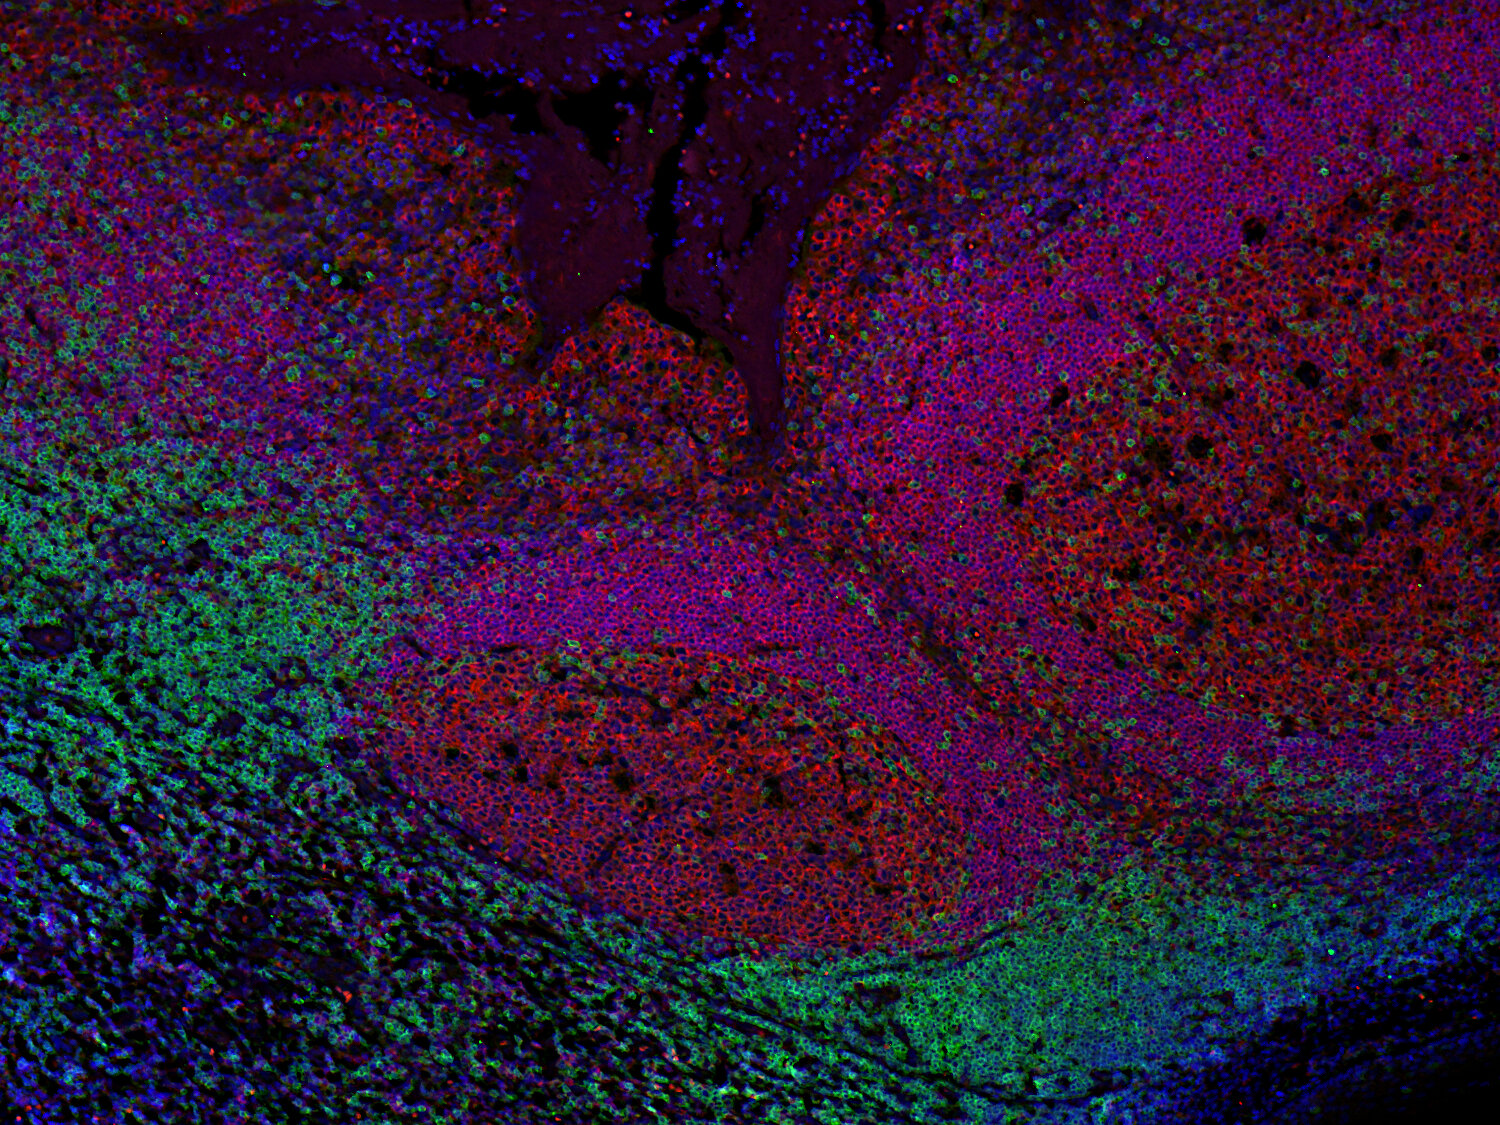

Immunofluorescence image of a human FFPE tonsil section stained for CD19 (B cells, red) and CD3e (T cells, green)